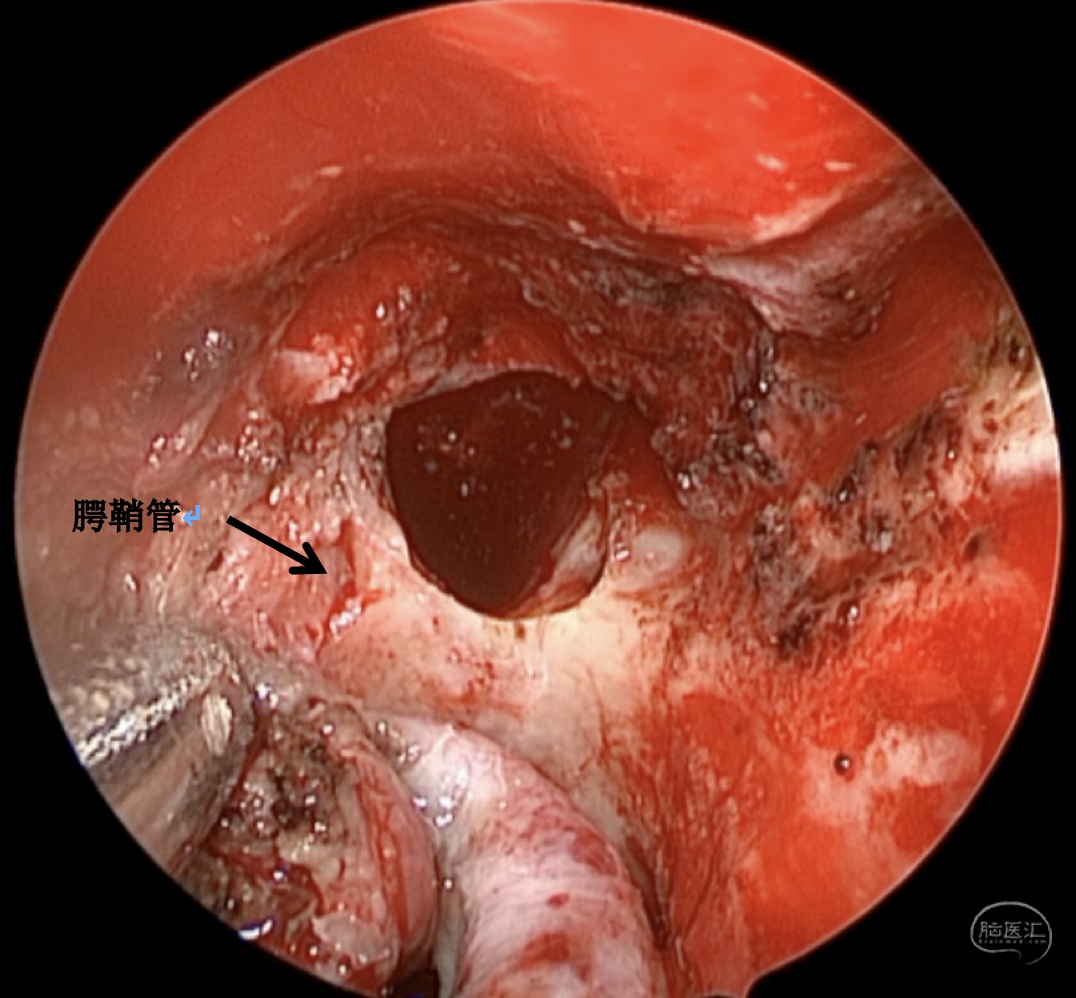

手术方案:内镜经鼻经翼突入路

术中情况:

蝶窦可向翼突根方向过度气化,位于翼管-圆孔连线之外的蝶窦腔隙,称作蝶窦外侧隐窝,是自发性脑脊液漏和脑膜脑膨出的高发区域。蝶窦外侧隐窝脑膜脑膨出伴脑脊液漏在临床上相对少见,这种脑膜脑膨出,如果在出生时出现往往较大,是因为在胚胎形成过程中,神经管未闭所导致。然而,较小的脑膜脑膨出可以多年都不被发现,或者由于外伤、医源性损伤、颅底侵蚀(炎症或者肿瘤)而发生。此外,由于各种原因的颅内压增高,迫使脑组织通过蝶骨的先天性薄弱区疝出,也可以导致该这种疾病发生,本例患者应属于这种情况。

蝶骨在胚胎期由5块软骨板融合形成,如果融合不完全,就会导致先天性骨质缺损。最常见的缺损位于蝶骨大翼,形成一个恒定的外侧颅咽管,也称为Sternberg管,它由Sternberg医师于1888年首先描述。